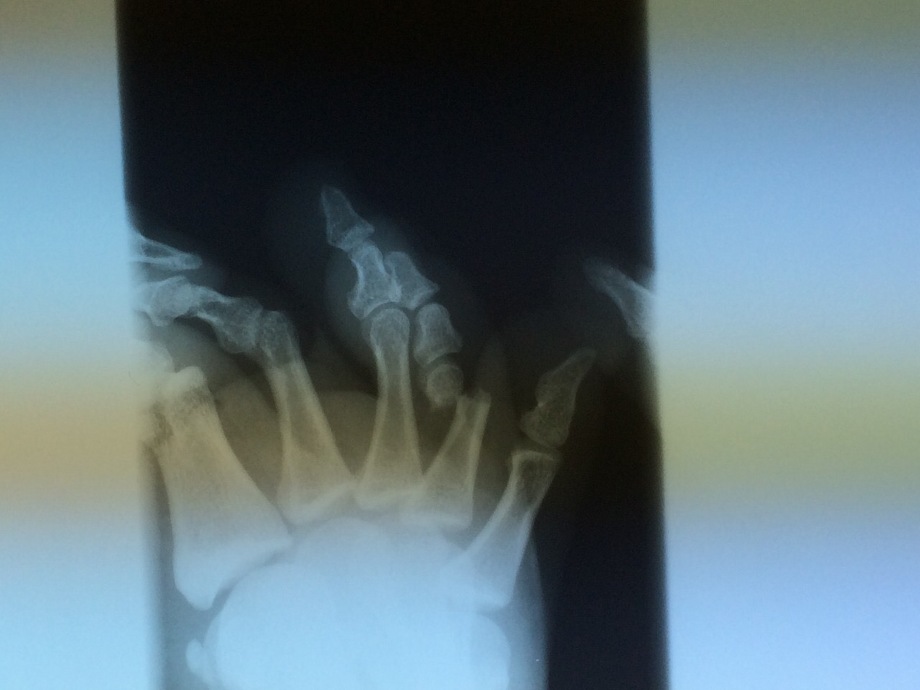

右足第四指基節骨骨折

先日、長男(16歳)が学校の体育でサッカーをやっていた際に足を蹴られてしまい「右足第四指基節骨骨折」をしてしまいました。

左側の骨の画像の右から二本目の指を上から見ていくと折れている部分がありますね。

完全にポッキリ折れています。

これは横から撮影した画像なんですが、完全にずれて折れた部分が下に落ちています。

この日は一度医師に整復してもらったんですが、うまく整復出来なかった為翌日総合病院に行くよう言われました。

総合病院では医師2人がかりで整復をしていただきなんとか整復が出来たようです。